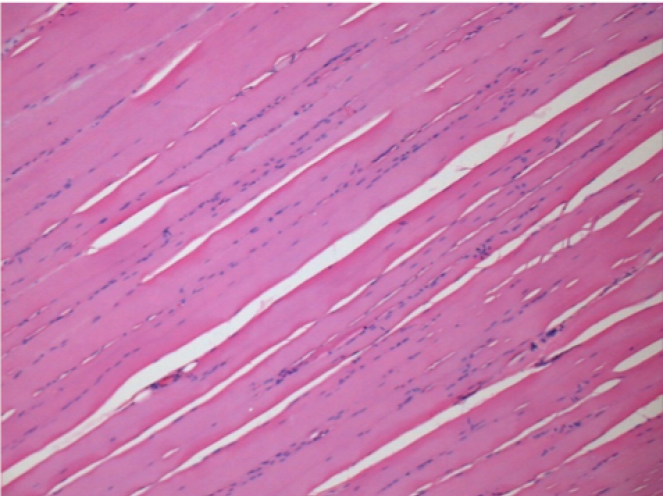

7 місяців (210 днів) після ін'єкції 0,1 мл Ендопіл в правий претибіальний м'яз.

Повна Restitutio ad integrum через 7 місяців

Л :Контроль 50x210 днів

П:50X-210 днів